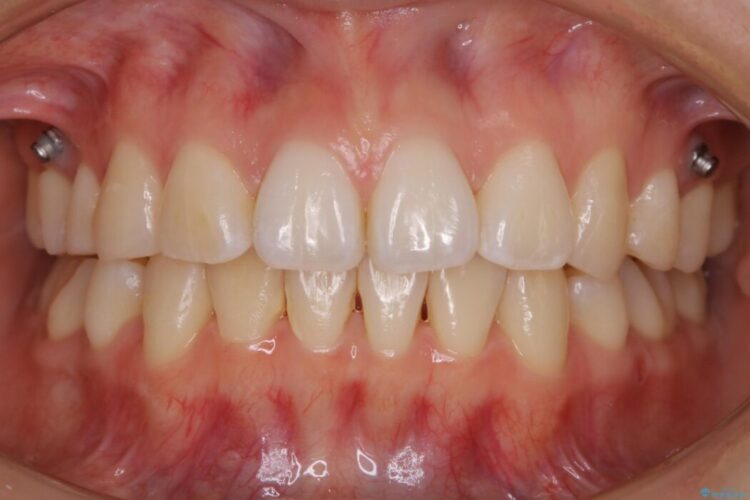

治療後について

後戻りしていた歯列もきれいに整い患者様にはご満足いただけました。